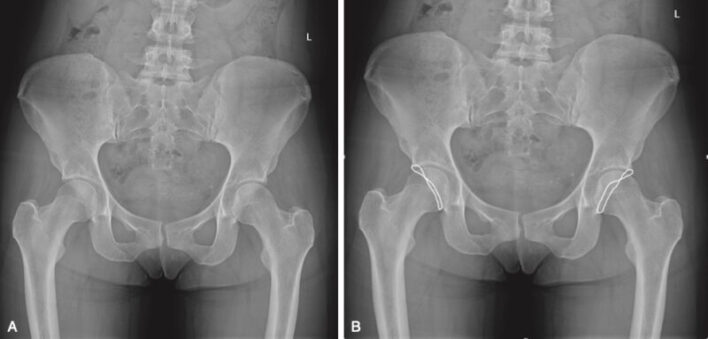

Chụp X quang thường quy (thẳng, nghiêng) vẫn là thăm dò cơ bản trong đánh giá đau khớp háng. Ở những người bị đau vùng bẹn hoặc rách ổ cối, ít nhất một bất thường về xương phù hợp với FAI xuất hiện ở 94,3% và 87% trong các nhóm này. Ở nam, góc alpha tăng và ở nữ giới, độ Tonnis hoặc góc thân – cổ xương đùi giảm có liên quan đến rách sụn viền lớn hơn.

FAI loại gọng kìm có thể là do sự bao phủ quá mức chỏm xương đùi tổng thể do ổ cối quá sâu hoặc do sự che phủ quá mức khu trú liên quan đến ổ cối vặn hướng ra sau (acetabular retroversion). Trên phim X quang khung chậu trước-sau, ổ cối bình thường bao phủ ít nhất 75% chỏm xương đùi (ilioischial line). Ổ cối sâu là khi hố ổ cối hoặc chỏm xương đùi nhô ra phía trong đường chậu ngồi. Vặn ổ cối ra sau khu trú được gợi ý bởi dấu hiệu chéo (cross over sign), trong đó phần đầu của thành ổ cối phía trước nằm ở phía bên ngoài của thành ổ cối sau. Chụp X quang nghiêng có thể cho thấy hẹp khe khớp sau dưới.

Dấu hiệu X quang cơ bản của FAI loại chỏm là giảm khoảng cách rìa xiên cổ – chỏm xương đùi ở phía trước hoặc trên, làm cho điểm nối cổ – chỏm xương đùi có vẻ phẳng hoặc lồi thay vì lõm. Đặc điểm này thường được gọi là biến dạng tay cầm súng lục.

“pistol grip”)